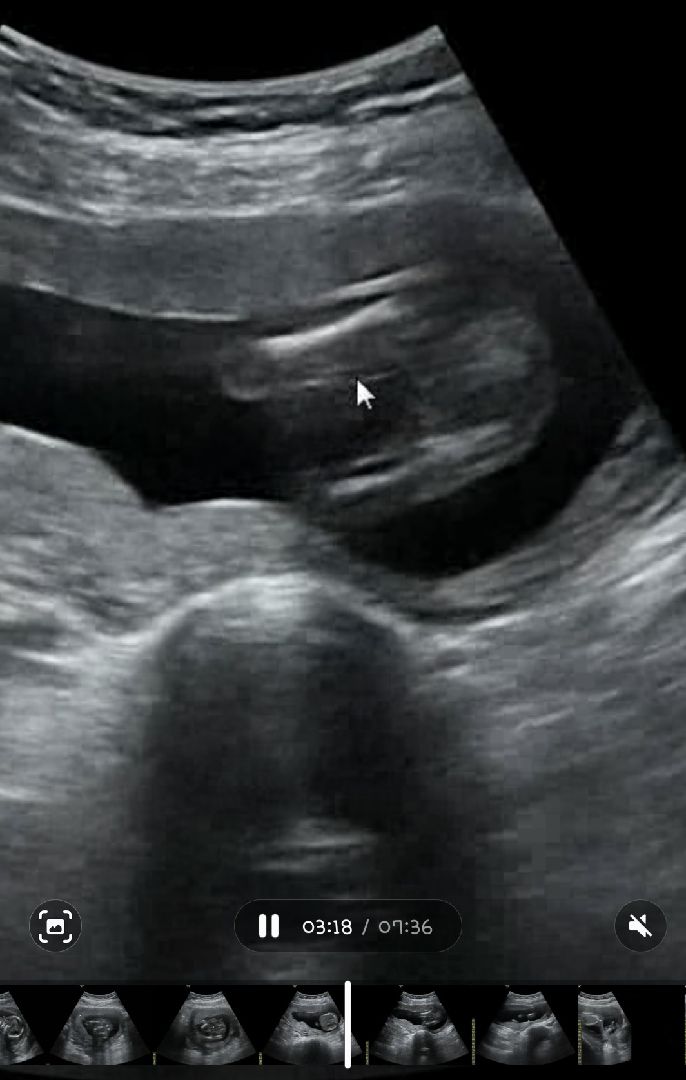

16주차 성별..

제 아이의 성별은 뭘까요? 원장님이 아직은 보이는게 없다던데.. 나중에 성별반전이 있을까요?

딸 같아요 ㅎㅎ 저 16주때는 이미 고추가 툭 보여..

딸같은데 확실치않네요

엇 갈라진건 딸같은데..!!근데원장님의 확언이더해져야ㅠ